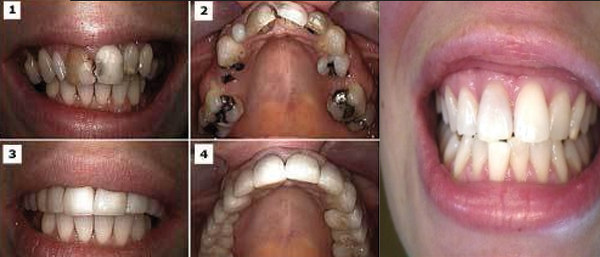

പോട് വന്ന് അത് ആഴത്തിൽ ബാധിച്ച് പല്ലിന്റെ ഉള്ളിൽ രക്തക്കുഴലുകളും ഞരന്പുകളും അടങ്ങുന്ന പൾപ്പിൽ എത്തുന്പോഴാണ് റൂട്ട് കനാൽ ചികിത്സ നടത്തേണ്ടതായി വരുന്നത്. ഇനാമലിന്റെയും ഡെന്റയിന്റെയും കട്ടി കുറഞ്ഞ് പൾപ്പുമായി അടുത്തു നിൽക്കുന്ന സാഹചര്യങ്ങളിലും റൂട്ട് കനാൽ നടത്താൻ നിർദേശിക്കാറുണ്ട്. പോടിന്റെ വിവിധ ഘട്ടങ്ങളും ചികിത്സയും:

പോടിന് ആഴം കൂടുതൽ ആണെങ്കിൽ റൂട്ട് കനാൽ ചികിത്സ നടത്തേണ്ടതായി വരും. ഈ ഘട്ടത്തിലാണ് ദന്ത പരിശോധയ്ക്കായി സമയം കണ്ടെത്തുന്നത്.

ഇവിടെ റൂട്ട് കനാൽ ചികിത്സ അല്ലാതെ ഒരു ചികിത്സയേ ഉള്ളൂ; അത് പല്ല് എടുത്തുകളയുക എന്നതു മാത്രം ആണ്. വേദനയും ബുദ്ധിമുട്ടുമില്ലാതെയാക്കാൻ റൂട്ട് കനാൽ ചികിത്സ സഹായിക്കും.ഇതിനുശേഷം പല്ല് പഴയ രീതിയിൽ ഉപയോഗത്തിൽ കൊണ്ടുവരാൻ ക്യാപ്പുകൾ ഇടേണ്ടതായി വരും. ഉറപ്പും ബലവും കുറവാണ് എങ്കിൽ പോസ്റ്റും കോറും ചെയ്താൽ പരമാവധി ബലം ഉറപ്